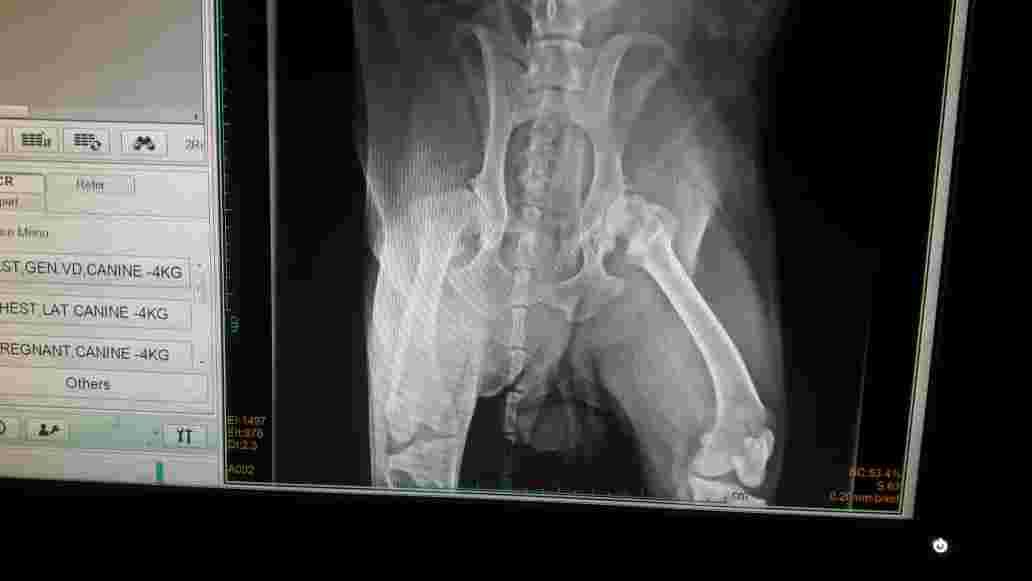

As you seen that attach xray my 7 yr labrador is eating but throwing up...doctor said he has pain in his leg I dont know what to do ? He lose 10 kg so please tell me is it life threatening or what because he is crying also i can see wet something coming out of eyes

Hi, thanks for using Petco Pet Education Center, formerly Petcoach! Did your vet take belly X-rays? If he is vomiting and has lost over 20 pounds. he needs X-rays of his belly and blood work. He does have very bad hips but that shouldn’t cause vomiting and weight loss. You need to follow up with your vet today. Good luck!